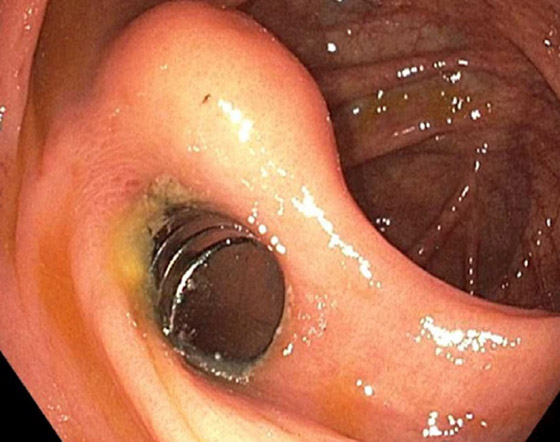

لقد بدوا بشكل مثير للريبة مثل مغناطيس النيوديميوم الفائق القوة، حيث أن المغناطيسات كانت موجودة في قرحة في جدار المعدة لفترة كافية لبدء التسبب في بعض الضرر. وتمت إزالة المغناطيسات بسهولة نسبية باستخدام ملقط وشبكة جراحية صغيرة، إلا أن المزيد من التحقيقات خلال اليومين التاليين أظهرت أن عملهم لم ينته بعد. وسرعان ما تم اكتشاف المزيد من المغناطيسات تتحرك عبر الأمعاء الغليظة، حيث ظهرت بالفعل علامات التعفن.

وعلى الرغم من إمكانية إزالة ثلاثة منها أثناء تنظير القولون، إلا أن الباقي يتطلب عملية جراحية، حيث تم الكشف عن 15 مغناطيسًا إضافيًا. ويبدو أن المغناطيسات ضغطوا جزءا من الأمعاء الغليظة والدقيقة بالفعل وبدأوا بصنع ثقب في الأمعاء. ليست هناك حاجة لشرح العواقب المروعة للأمعاء المثقوبة. ولحسن الحظ، فإن إزالة المغناطيس وبعض المضادات الحيوية في الوقت المناسب منعت المراهق من الشعور بألم ثقب في أمعائه وتسريب محتوياته إلى بطنه.